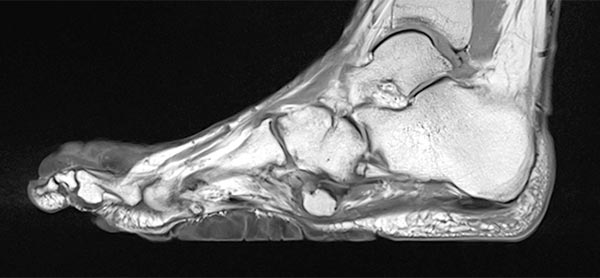

Präoperative Abklärung des Bindegewebsnävus in der MRT, hier sagittale T2-gewichtete, fettunterdrückte Sequenz des rechten Fußes. Der Bindegewebsnävus ist aufgrund des hohen fibrotischen Anteils homogen hypointens (schwarz).

Auch in der nativen, T1-gewichteten MRT sagittal ohne Kontrastmittel (gleiche Schnittebene) ist der Bindegewebsnävus homogen hypointens (schwarz).